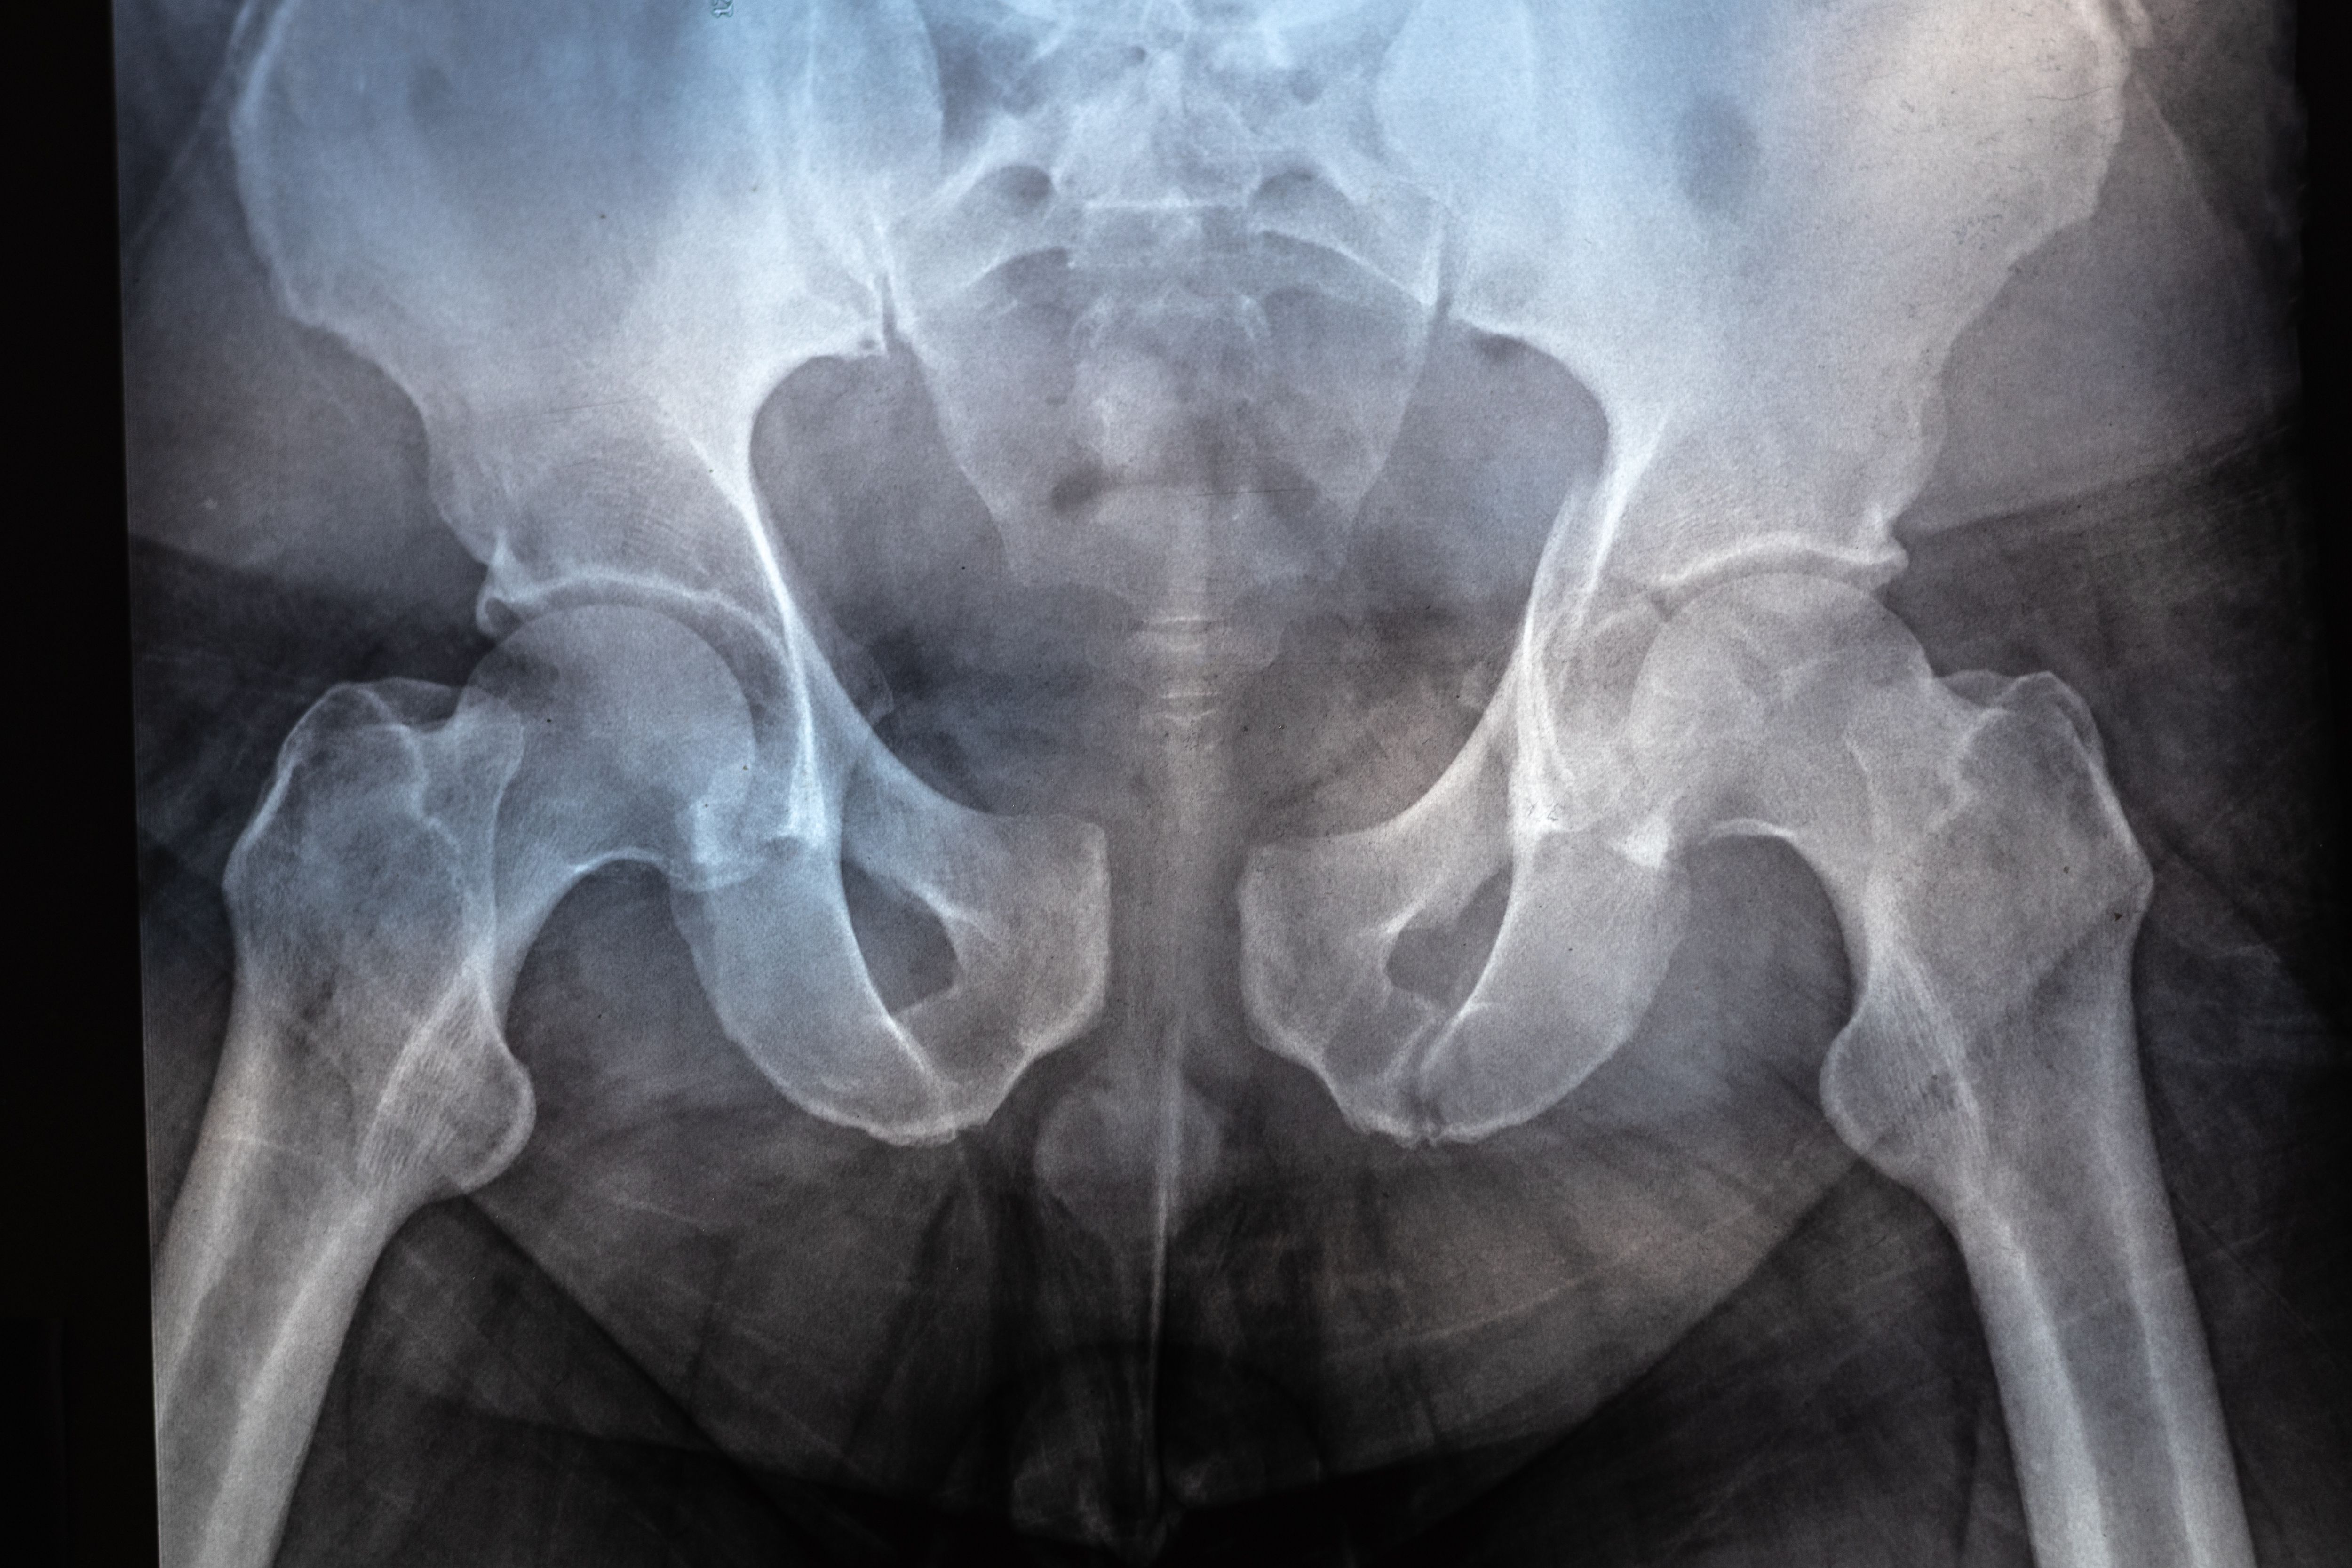

Pelvis wellness has gained attention over the years primarily as a women's health issue. However, recent studies and wellness programs emphasize that pelvis health is crucial for everyone, regardless of gender. The pelvis is fundamental to numerous bodily functions and ensuring its health can lead to improved quality of life.

Men often overlook pelvis health, yet it plays a vital role in core stability, bladder function, and sexual health. Conditions such as pelvic pain, incontinence, and erectile dysfunction can stem from poor pelvis health. A dedicated wellness program can help men address these issues and enhance their overall well-being.

While there are gender-specific concerns when it comes to pelvis health, many aspects are universally beneficial. A strong pelvis supports overall body mechanics, aids in posture, and helps prevent injuries. These benefits highlight the importance of inclusive wellness programs that cater to all genders.